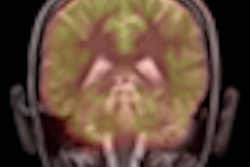

MRI and CT are advancing rapidly in so many areas that it's often tempting to write off long-established techniques that seem outdated and unfashionable. But sometimes old methods are dismissed prematurely, as appears to be the case with technetium-99m sestamibi myocardial perfusion scanning in the assessment of myocardial function.

Sestamibi is a radioisotope imaging technique that has been around for many years, but a new study from a leading London hospital suggests that it still has a valuable role for assessing myocardial viability. To find out more, visit our Molecular Imaging Digital Community, or click here.